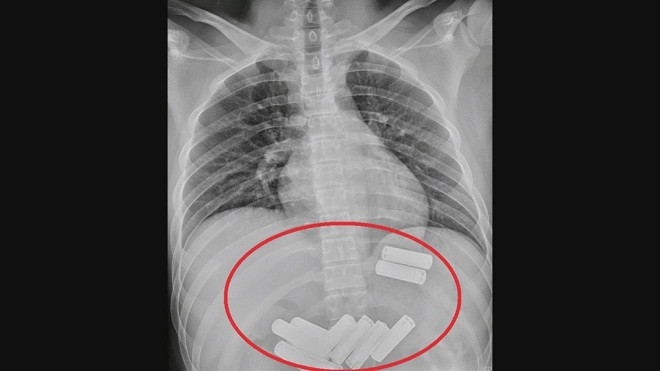

Hình ảnh chụp X-quang cho thấy, trong dạ dày Lee có 11 viên pin AA. Bác sĩ Lin Te-fu tại Khoa Tiêu hóa và Gan mật thuộc Bệnh viện Đa Khoa Da Chien cho hay, phần lớn các ca nuốt phải dị vật xảy ra ở trẻ em. Tuy nhiên, người trưởng thành cũng có nguy cơ nuốt dị vật, nếu họ say rượu.

Ông Lin cho hay, khi nội soi dạ dày của Lee, các bác sĩ phát hiện bên trong có nhiều viên pin. Các bác sĩ đã mất khoảng một tiếng để lấy từng cục pin ra khỏi dạ dày. Sau khi trải qua nội soi đau đớn, Lee khẳng định, “tôi sẽ không bao giờ dám làm điều đó thêm một lần nữa".